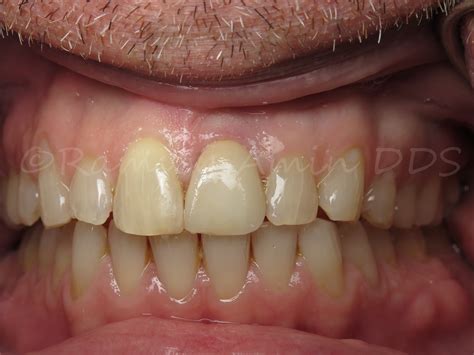

• Natural Appearance: Modern implant crowns are crafted from high-quality porcelain or zirconia, which mimics the translucency and color of natural teeth.

The success of an implant in the front of the mouth often depends on the quality of the surrounding gum tissue. Surgeons pay special attention to the "emergence profile," which is how the crown emerges from the gum line, ensuring it looks identical to a natural tooth rather than a prosthetic attachment.

Restoring a missing front tooth is an investment in your self-esteem and your long-term oral health. By selecting dental implants, you are choosing a solution that is durable, aesthetically pleasing, and biologically compatible with your natural anatomy. Whether you have lost a tooth due to injury, decay, or periodontal disease, consulting with an experienced implant specialist can help you determine if you are a candidate for this life-changing procedure. Remember that every smile is unique, and personalized treatment plans are the key to achieving that perfect, natural-looking result you desire. Taking the step to replace your missing tooth will not only enhance your smile but will also provide the structural support your mouth needs for years to come.